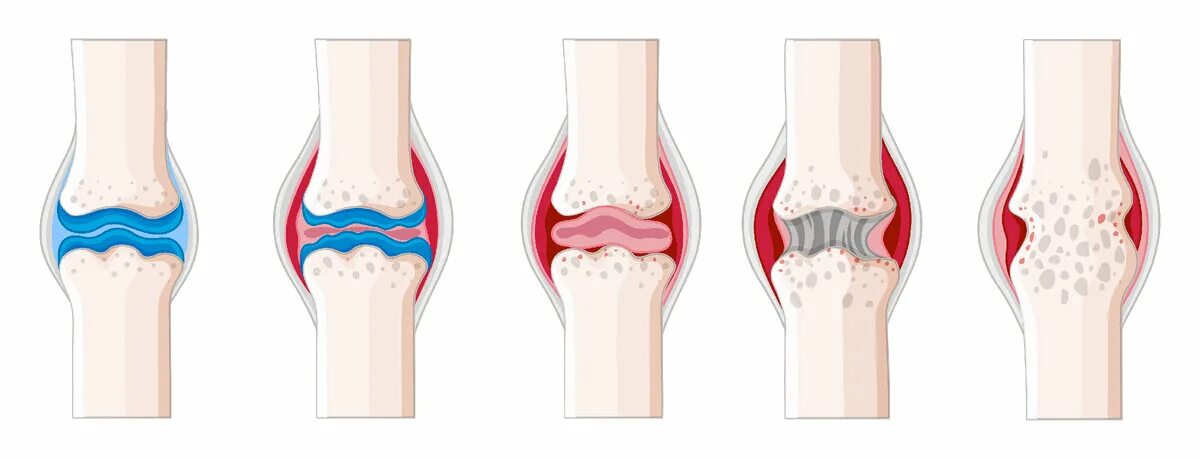

Остеоартрит 2025